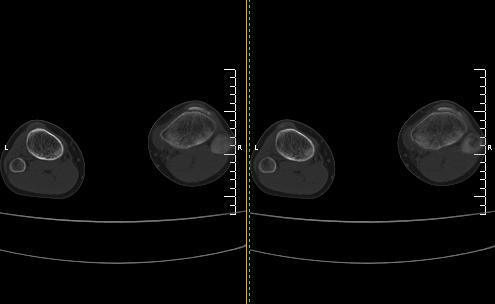

标题: CT19091:右胫骨近段骨性突出.

男,15岁,右胫骨近段软组织肿胀,下肢疼痛10左右.

支持考虑右胫骨内髁骨软骨瘤,不除外基底部骨折可能。

右胫骨近端内侧骨性突起,皮质连续,骨质结构正常,首先考虑胫骨骨软骨瘤,随访观察。